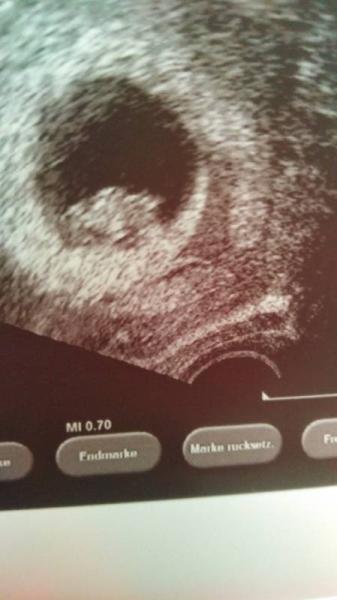

Guten Morgen, leichte Übelkeit lässt mich mal wieder nicht schlafen...... Ich möchte mich gerne bei Euch wieder einreihen. Leider hatte ich im Juni bereits eine frühe Fehlgeburt und auch bis zum Schwangerwerden gab es einige Hürden. Nun hat es wie ein Wunder wieder spontan auf natürliche Weise geklappt. Mein Sohn wurde 09/12 geboren. Wir freuen uns sehr, allerdings belasten mich vorangegangene Fehlgeburten schon sehr. Jedoch war ich bei diesen nie bis zum Herzschlag gekommen.... Positiv testen durfte ich nach unserem Urlaub ab 16.08. Am 02.09 bestätigt die FA Fruchthöhle mit Inhalt. Letzten Donnerstag schlägt das Herz bei 7+6. Es sieht bisher alles gut aus. Allerdings sitzt mir die Angst im Nacken es könnte wieder negativ ausgehen.....Ich weiß es wird mich die ganze Schwangerschaft über begleiten. Da ich Erzieherin bin habe ich es bereits auf der Arbeit sagen müssen und bin im Beschäftigungsverbot. Mein nächster Termin ist erst am 10.10.ich weiß gar nicht wie ich das bis dahin aushalten soll. Ich würde mich freuen wenn ihr mich hier aufnehmt. LG Atti

Bild zu Ich setze mich mal vorsichtig! - Forum für April - Mamis